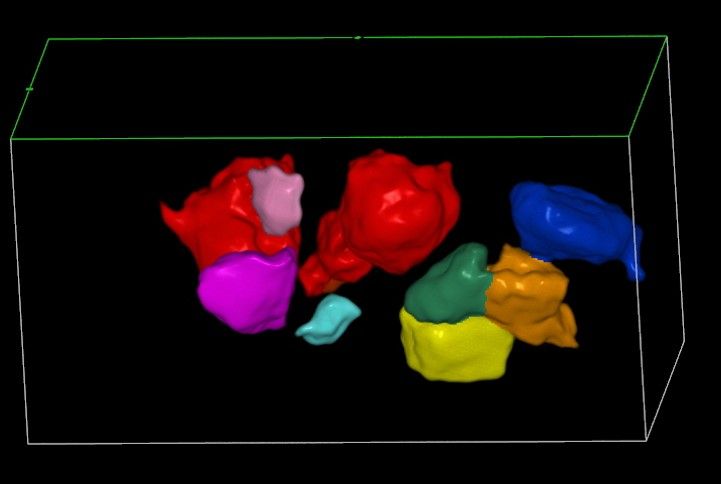

Современные экспертные УЗИ сканеры дают возможность проводить исследования всех органов в 3D. Это позволяет, используя полученный массив данных, получать диагностические сечения в любой плоскости, недоступной для обычного 2D УЗИ. Наиболее интересной является фронтальная. Например, визуализация полости матки. Диагностическая возможность выявления пороков развития превосходит все другие методы (рентгеновские и МРТ). Метод также позволяет уточнить положение ВМК (спирали) в полости матки, расположение миоматозных узлов, расположение плодного яйца на малых сроках, полипов. Сегодня современное экспертное ультразвуковое исследование невозможно без использования 3D УЗИ.